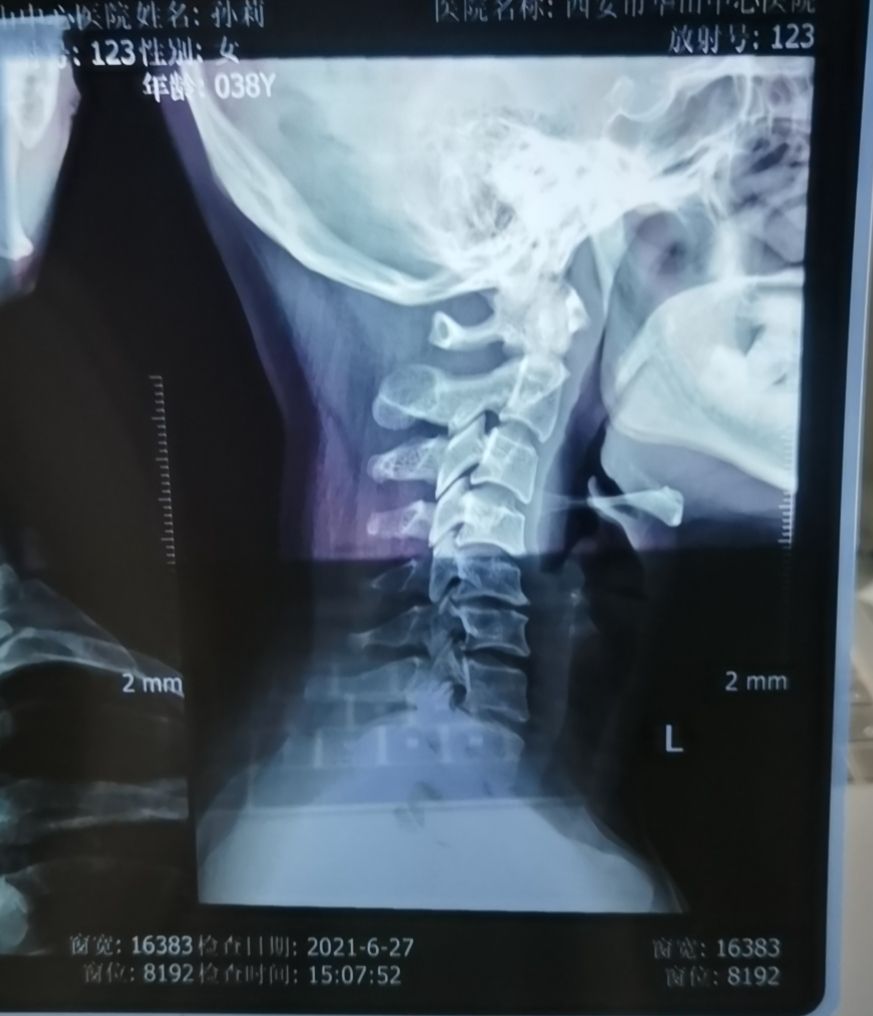

我的假宽胯第一次调整

4.下图是我的颈椎片子,懂的人看到,都知道很严重!生理弯曲完全反过来了!拍片子的医生都说,你的脖子咋长成这样了[抠鼻R][鄙视R]哎,我也不知道我是怎么把我脖子虐待成这样的!总之,颈椎问题已经伴随我多年,左手拇指震颤,右侧胳膊时不时疼痛,夜不能寐!时而痛的无法工作,时而缓解,但总得趋势是犯得越来越频繁,症状越来越多!!哎我是有多么不爱自己,这么多年都不管他!医生告诉我可以通过整脊恢复生理弯曲![黄金薯R]不过需要一段时间,所以我准备先做10次看看!第一次的整脊,脖子感受比较小,毕竟多年的问题,但是明显感觉颈部轻松很多!期待

我可怜的颈椎:生理弯曲完全反了